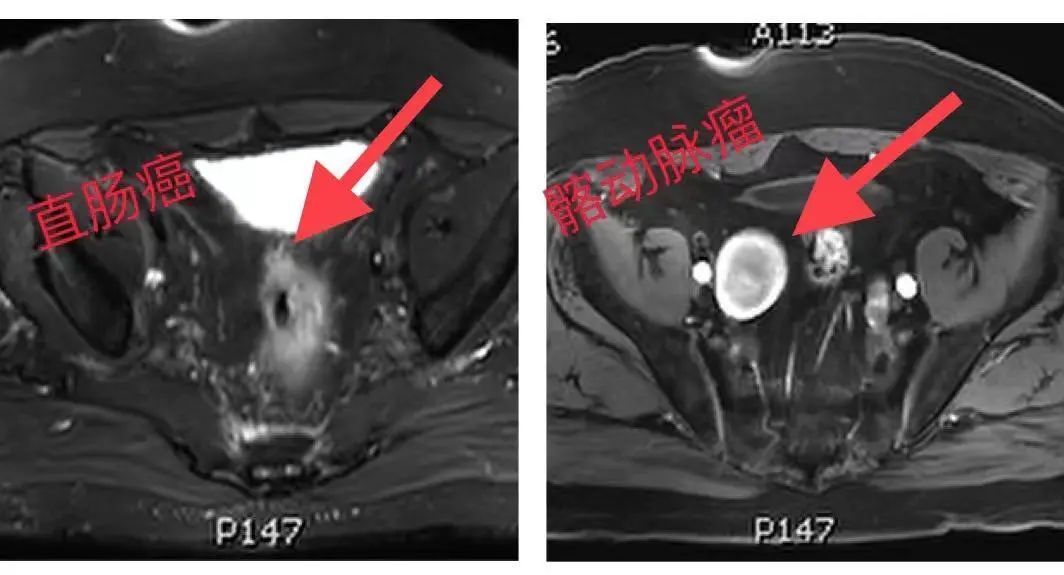

入院后安排术前检查,贺老伯为高龄患者,有高血压病史,基础状态差,早搏,心功能不全,左前降支、第1-3对角支、左旋支、第1顿缘支及右冠状动脉、锐缘支管壁多发钙化及非钙化斑块,管腔局部重度狭窄,CT报告又发现髂内动脉上有个巨大的血管瘤,请MDT会诊。

髂动脉瘤是常见的周围动脉瘤,易造成髂动脉动脉壁的异常扩展,一旦髂动脉瘤破碎,多数会引来严重的大出血。目前肠镜是明确肠癌的唯一手段,如果行肠镜检查,瘤体很可能会被肠镜压迫导致破裂大出血,随时可能危及患者生命。如果不做肠镜,则会影响术中对肿瘤的评估及定位。由于贺老伯疾病的特殊性,为进一步明确动脉瘤范围及与周围组织情况,制定下一步手术方案。傅传刚教授请血管外科、呼吸内科、麻醉科、重症监护室会诊,协助评估手术风险,制定各种应对措施。拆除“*弹炸**”是当务之急。同时,直肠癌手术有很大的风险和难度,对术者、麻醉医生及病人都是巨大挑战。对于手术方案各科有很大争议,为了确保手术能安全顺利地拿下,和血管外科冯翔教授一起会诊讨论后决定,贺老伯髂动脉瘤诊断明确,高龄,同时合并肠癌,结合患者各项条件合适,已达手术指征。